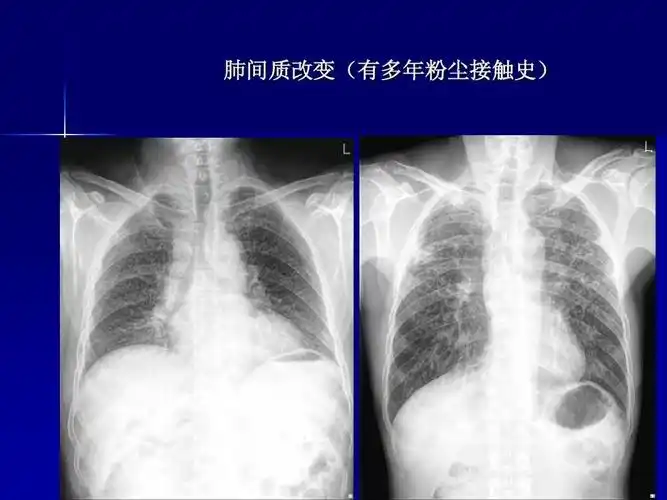

肺部正常和x线异常表现ppt

肺部异常的胸片 左肺切除术后